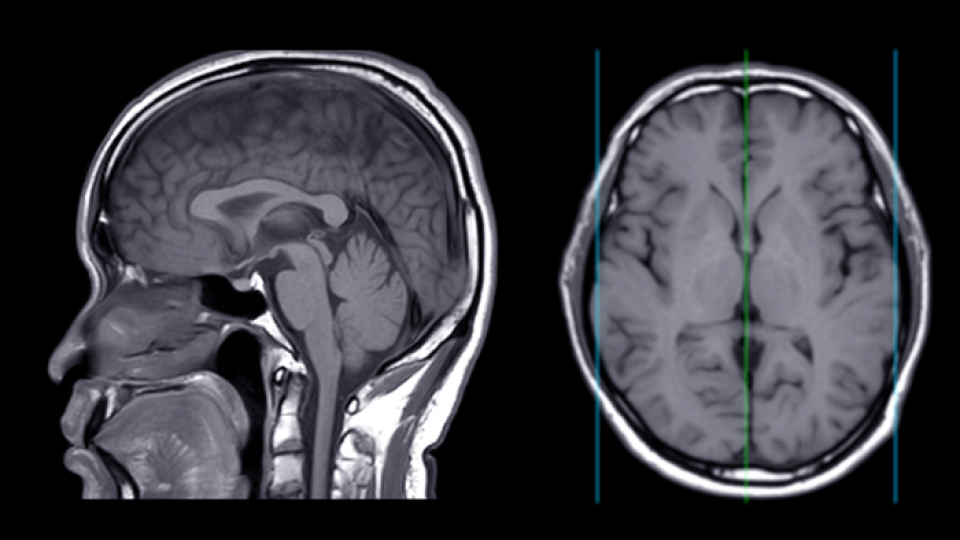

놀랍게도 아닙니다! 드라마 속 클라우드 세포종은 덩어리지지 않고 넓게 퍼져나가는 악성 뇌종양을 묘사하기 위해 구름이라는 이름을 붙힌 허구의 질병입니다.

다만 모티브로 삼았다고 볼 수 있는 유사한 질병이 현실에도 있는데요, 바로 교모세포종입니다.

그럼에도 불구하고 해인은 독일 암센터로 가 치료를 받지만 수술 후 부작용으로 일부 기억을 잃은 모습을 보입니다. 실제로 교모세포종은 종양의 경계가 불분명하고 빠르게 퍼져나가 치료가 쉽지 않습니다.

대부분 조기에 발견해 수술을 하면 완치가 되는 다른 종양들과 달리 교모세포종은 완전히 종양을 제거하는 것이 사실상 불가능해 수술 이후에도 계속해서 방사선 치료와 항암 치료를 병행해야 합니다.